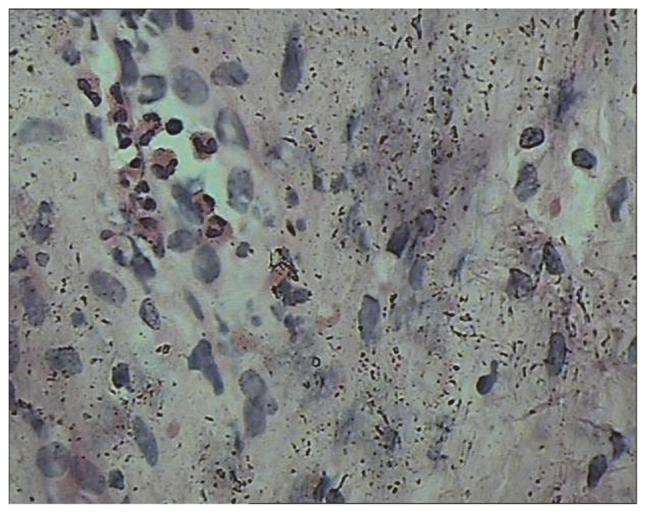

The aim of the present case report was to investigate the clinical features, pathological examination and treatment of eosinophilic cystitis (EC) in children. Two cases of EC were reported and reviewed from January 2016 to March 2017. Case 1 (male; 6 years old) had intermittent hematuria, frequent urination, urgent urination, difficulty in urination and abdominal pain. Case 2 (male; 7 years old) had frequent urination, urgent urination, urinary pain, dysuria and suprapubic pain with no hematuria. One patient had a history of allergies and both patients underwent a cystoscope biopsy. Blood eosinophils were clearly increased and a bone marrow biopsy examination revealed that marrow eosinophils were also increased in both cases. The urine culture results were negative. Ultrasonography and computed tomography revealed uneven thickening of the bladder wall and diffusive mucosal lesions. Cystoscopy revealed that the bladder volume became smaller and the mucosa at the bladder floor and neck was red. Lesions were biopsied through the urethra and the following characteristics were observed: Congestion and edema of the bladder mucosa, infiltration of the blood vessels and eosinophils in the muscular layer, accompanied by focal muscle necrosis. Patient 1 was administered anti-inflammatory and cetirizine hydrochloride treatments, followed by 6 weeks of prednisone dose-reduction therapy. Patient 2 was administered antibiotics and cetirizine hydrochloride. Following 6-month follow-ups, abnormal voiding symptoms had disappeared in each case. Ultrasonography and computed tomography revealed no bladder wall thickening or space-occupying lesions. EC in children is rare and easily misdiagnosed as nonspecific bladder inflammation or bladder occupying lesions. Cystoscopy and biopsy are necessary to diagnose EC and conservative treatments with anti-inflammatory, anti-allergic and cortical hormone nonspecific treatments are suggested.

本病例报告的目的是探讨儿童嗜酸性膀胱炎(EC)的临床特征、病理检查及治疗方法。报告并回顾了2016年1月至2017年3月期间的2例EC病例。病例1(男,6岁)有间歇性血尿、尿频、尿急、排尿困难及腹痛症状。病例2(男,7岁)有尿频、尿急、尿痛、排尿困难及耻骨上疼痛,无血尿症状。1例患者有过敏史,2例患者均接受了膀胱镜活检。两例患者血液嗜酸性粒细胞均明显增多,骨髓活检显示骨髓嗜酸性粒细胞也增多。尿培养结果为阴性。超声和计算机断层扫描显示膀胱壁不均匀增厚及弥漫性黏膜病变。膀胱镜检查显示膀胱容量变小,膀胱底部和颈部黏膜发红。通过尿道对病变进行活检,观察到以下特征:膀胱黏膜充血水肿,肌层血管及嗜酸性粒细胞浸润,伴有局灶性肌肉坏死。患者1接受抗炎及盐酸西替利嗪治疗,随后进行6周的泼尼松减量治疗。患者2接受抗生素及盐酸西替利嗪治疗。经过6个月的随访,两例患者的排尿异常症状均消失。超声和计算机断层扫描显示无膀胱壁增厚或占位性病变。儿童EC较为罕见,易被误诊为非特异性膀胱炎症或膀胱占位性病变。膀胱镜检查及活检对于诊断EC是必要的,建议采用抗炎、抗过敏及皮质激素等非特异性保守治疗方法。